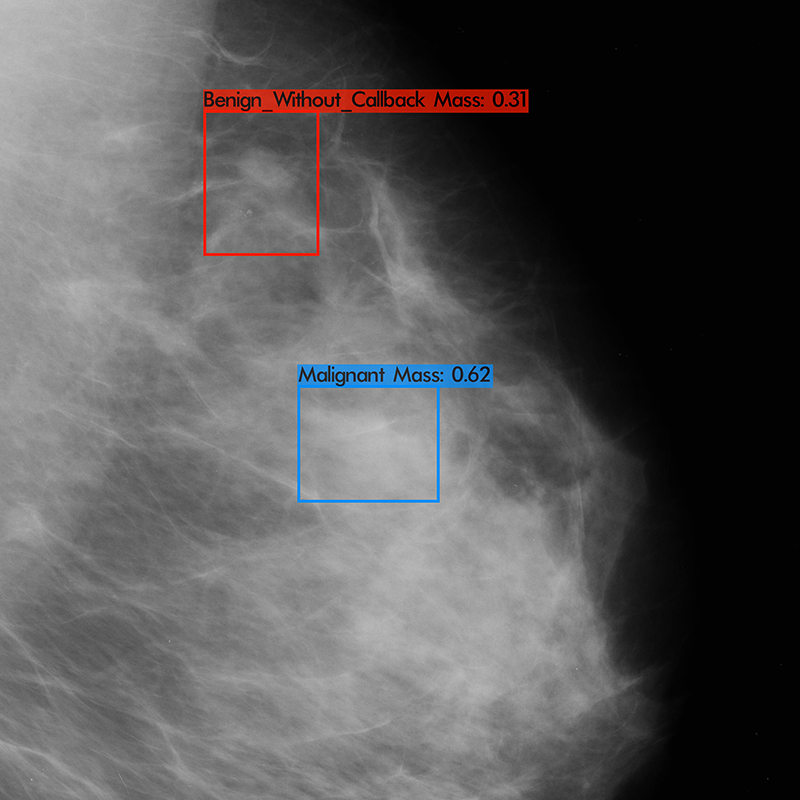

Screening mammogram of a 47 year old female. Left breast MLO view demonstrating two lesions detected by RADIFY®. One benign lesion and a second mass with malignant features confirmed on ultrasound and biopsy.